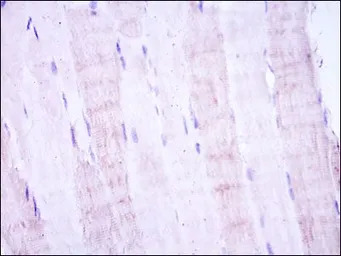

IHC-P analysis of human muscle tissue using GTX60399 SEK1 / MKK4 antibody [5H4].